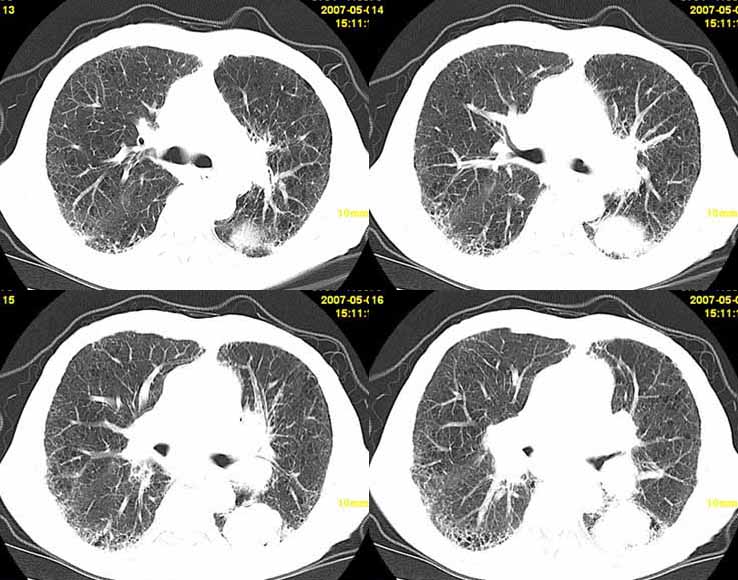

以下是引用小初学者在2007-5-12 11:09:00的发言:[br][br]双肺弥漫性质纤维化(考虑矽肺所致),并发左肺下叶背段周围性肺癌纵隔淋巴转移。

以下是引用zhangzhongshou在2007-5-12 12:09:00的发言:[br]1、左下叶背段周围型肺癌左肺门及纵隔淋巴结转移可能性大。[br]2、弥漫性肺气肿(双侧)。[br]3、双肺间质纤维化。

以下是引用老爱克斯新网客在2007-5-12 12:54:00的发言:[br]1周围型肺癌纵隔肺门淋巴结转移,2肺间质纤维化,